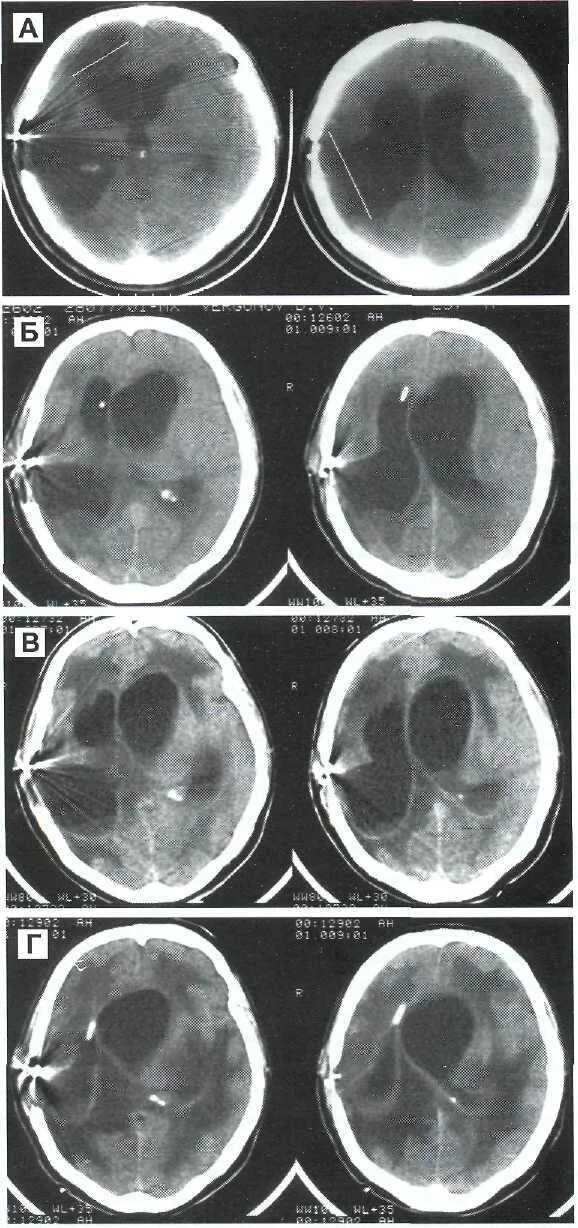

Гиподенсивное образование что это значит